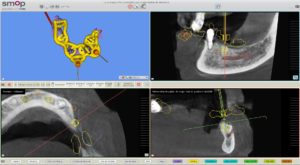

La planification implantaire a été réalisée sur le logiciel SMOP. Les empreintes ont été superposées avec le cone beam du patient.

Les implants ont été posés virtuellement, ce qui a permis au praticien d’évaluer la possibilité d’extraire, implanter et mettre en charge immédiatement lors d’une même séance.

Une fois la planification validée, un guide implantaire SMOP a été dessiné et imprimé (imprimante STRATASYS poly-jet avec précision à 16 microns ).

Le praticien a choisi de poser 2 implants Thommen en FULL GUIDED.